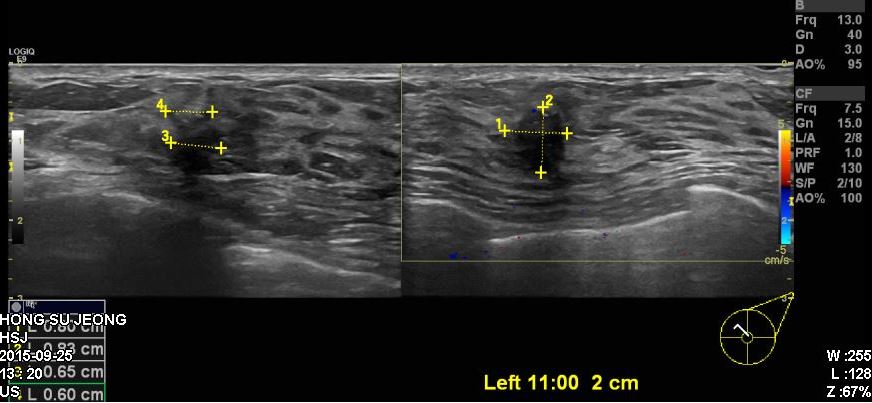

건진상 이상소견으로 내원하신 30대 환자분이십니다.

본원에서 추가로 시행한 유방초음파상 좌측 11시방향에 의심되는혹이있어

조직검사 시행하였고 결과상 침윤성유관암진단되었습니다.